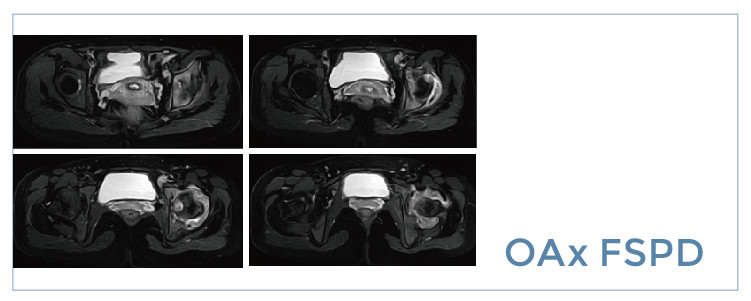

【朗润影像档案】20190809磁共振影像病例结果讨论